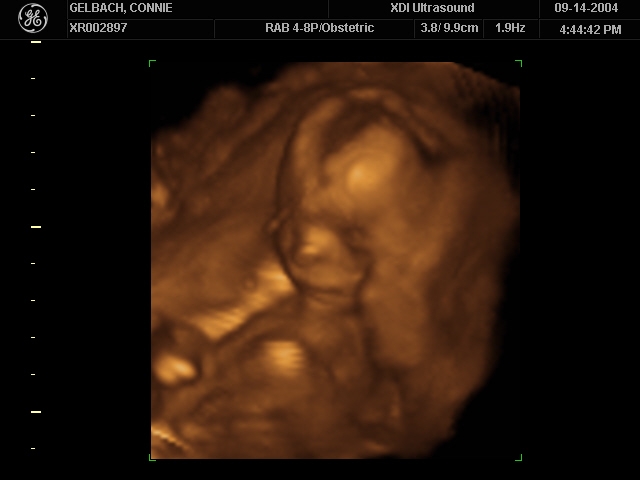

Sonograms